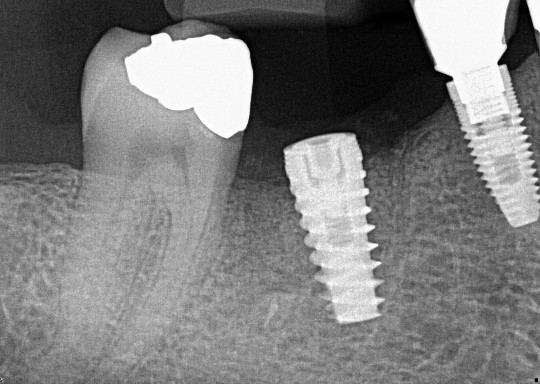

1. (Select ONE OR MORE correct answers)

The radiograph shows evidence of

2 / 50

2. (Select ONE OR MORE correct answers)